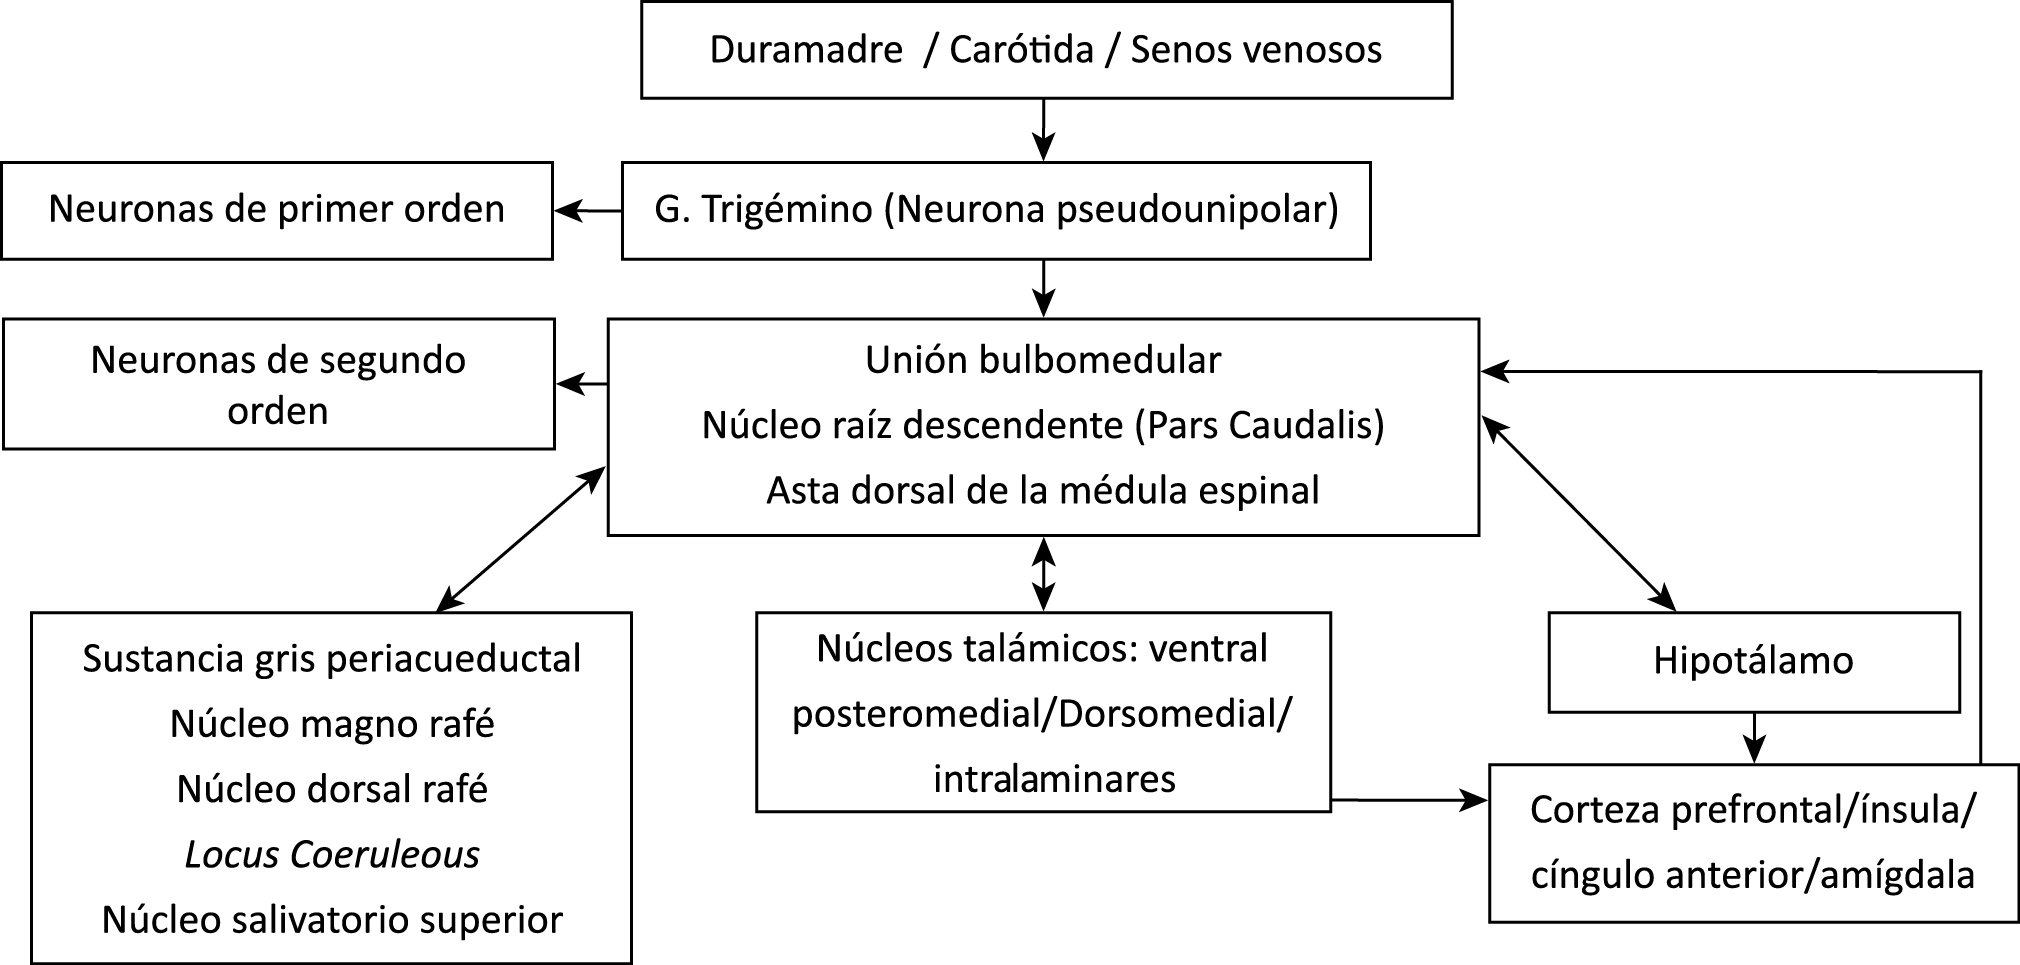

Todo lo mencionado contribuye al fenotipo del migrañoso y son vías que continuamente se están explorando para el desarrollo de nuevas terapias agudas y preventivas del dolor, más seguras y eficaces. Sin embargo, existe una controversia que gira en torno a dos cuestiones: la iniciación y el origen del dolor además de que todavía no se conoce el origen de los mecanismos neuronales que subyacen a la condición primaria en las personas susceptibles. Definitivamente la migraña implica la activación y sensibilización de las vías trigeminovasculares, así como el tronco cerebral y los núcleos diencefálicos(88). La vía aferente comienza en las aferentes vasculares nociceptivas de la duramadre que están para advertir, no para localizar. Su proyección al tálamo y la corteza y como se regula esta vía en cada nivel y por múltiples sistemas, ofrece la posibilidad de comprender los síntomas complejos y orientar las terapias. Los ataques comienzan como síntomas premonitorios, dificultad para concentrarse, bostezos, fluctuaciones del humor; y cambios homeostáticos, como la alimentación y el equilibrio de líquidos, que pueden incluir sensibilidades más generalizadas, como fotofobia y fonofobia. La fase premonitoria da paso a la fase de dolor con el sufrimiento acompañante y termina en una fase posdrómica de sentirse agotado por la experiencia. (Figura 1)

Un principio importante de esta teoría es que el desencadenante principal de la migraña proviene de la periferia, en los vasos sanguíneos de la duramadre, con la activación del sistema trigeminovascular proveniente del disparo de las neuronas trigeminales periféricas de primer orden en respuesta a una lesión nociceptiva o señales provenientes de las meninges que liberan mediadores neuroinflamatorios. La activación sostenida de las neuronas nociceptivas meníngeas durales provoca la activación secuencial y la sensibilización de las neuronas trigeminovasculares de primer orden (nociceptores periféricos), segundo orden (a nivel del TCC-complejo trigémino cervical) y tercer orden (trigeminotalámico), (Figura 5) así como la activación ascendente del cerebro, tallo y otras estructuras diencefálicas(97).

El dolor de cabeza asociado con un ataque de migraña, puede incluir la región frontal, temporal, parietal, occipital y cervical alta, es consecuencia de la activación del sistema trigeminovascular. (Figura 10)

La anatomía del sistema trigéminovascular ha sido bien descrita durante los últimos 70 años y esto ha ayudado a comprender la fisiopatología de la migraña y la distribución de su dolor. Se sabe que el cerebro es en gran parte insensible, pero un rico plexo de fibras nerviosas nociceptivas que se originan en el ganglio del trigémino inervan los vasos sanguí- neos de la piamadre, la aracnoides y la duramadre, incluidos el seno sagital superior y la arteria meníngea media, así como las grandes arterias cerebrales. (Figura 11) (23)

La inervación nociceptiva de la vasculatura intracraneal y las meninges incluye proyecciones axonales no mielinizadas (fibras C) y mielinizadas delgadas (fibras Aδ), principalmente a través de la división oftálmica (V1) del nervio trigémino, pero también, en menor medida, a través del nervio maxilar. (V2) y divisiones mandibulares (V3). También hay inervación neuronal de la duramadre desde los ganglios de la raíz dorsal cervical (24) (Figura 12).

Los terminales axónicos de las fibras nerviosas nociceptivas que inervan la duramadre contienen neuropéptidos vasoactivos CGRP, sustancia P, neurocinina A y péptido activador de la adenilato ciclasa pituitaria (PACAP)(25) (Figuras 13 y 14), que se cree que son liberados tras la estimulación que causa la vasodilatación de los vasos durales y piales(26) (Figura 15).

Hay una proyección aferente central desde el ganglio del trigémino que ingresa a la médula caudal del tronco encefálico, a través del tracto del trigémino, que termina en el núcleo espinal del trigémino caudalis (TNC), así como la médula espinal cervical superior (C1–C2). (Figura 16)

Las fibras nociceptivas Aδ y C terminan predominantemente en las láminas superficiales, I y IIo, así como en las láminas más profundas V–VI del TNC y extensión cervical. La estimulación de la vasculatura dural en modelos animales, incluidos los senos transverso y sagital superior y la arteria meníngea media, da como resultado la activación de las neuronas en las regiones TNC, C1 y C2 de la médula espinal cervical, conocidas en conjunto como el complejo trigeminocervical (TCC).

Estos datos sugieren que el núcleo del trigémino se extiende hasta el asta dorsal de la región cervical superior en un continuo funcional que incluye la extensión cervical, ello explica la distribución de la percepción del dolor en la migraña sobre las regiones frontal y temporal, además de la participación de parietal, occipital y regiones cervicales superiores(27).

Por lo tanto, se cree que la naturaleza intensa y pulsátil del dolor en la migraña es el resultado de la activación, o la percepción de activación, de estas entradas nociceptivas de las estructuras intracraneales y extracraneales, que convergen y se transmiten a través del TCC. (Figura 17)

Toda la información nociceptiva de las estructuras craneovasculares se transmite a través del TCC y mediante conexiones ascendentes a otras áreas del tronco encefálico y el diencéfalo, involucradas en el procesamiento del dolor y otra información sensorial. La activación de la vía antes mencionada contribuye a la percepción del dolor durante la migraña y también a los síntomas autonómicos, endocrinos, cognitivos y afectivos que duran todo el episodio migrañoso.

El procesamiento del dolor es complejo y está mediado por una red de estructuras neuronales que incluyen la corteza cingulada, las ínsulas y el tálamo(28). El tálamo está en el corazón del procesamiento central y la integración de la información nociceptiva y se considera un centro de retransmisión para manejar la información sensorial entrante e incluso modularla. Se cree que la llamada “matriz del dolor”, que incluye el tálamo, así como las áreas somatosensoriales primarias (S1) y secundarias (S2), la corteza cingulada anterior (CCA) y la corteza prefrontal, está involucrada en la integración de todos los sentidos, respuestas afectivas y cognitivas al dolor y se activan durante el procesamiento nociceptivo(28). (Figura 18)

Siendo el tálamo el centro principal para el procesamiento de la información nociceptiva sensorial en el cerebro, la transmisión de esta información para su procesamiento en las estructuras corticales donde los individuos la perciben es un factor clave. (Figura 18) Los tratamientos agudos como los “triptanos” (agonistas de los receptores 5-HT1B/1D)(29) y los antagonistas de los receptores CGRP(30) pueden inhibir las entradas nociceptivas durales agudas. Del mismo modo, los preventivos de la migraña propranolol(31), valproato de sodio(32) y topiramato(33)también pueden inhibir las entradas trigeminotalámicas nociceptivas durales en el VPM (Núcleo ventral posteromedial).